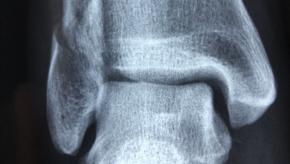

Read ArticlePlatelet-Rich Plasma Injections Fail in Ankle Osteoarthritis

A controlled trial of intra-articular platelet-rich plasma (PRP) injections into the ankle of osteoarthritis (OA) patients failed to improve ankle symptoms and function when compared to placebo injections - yet another trial showing that intraarticular injections are seldom beneficial.